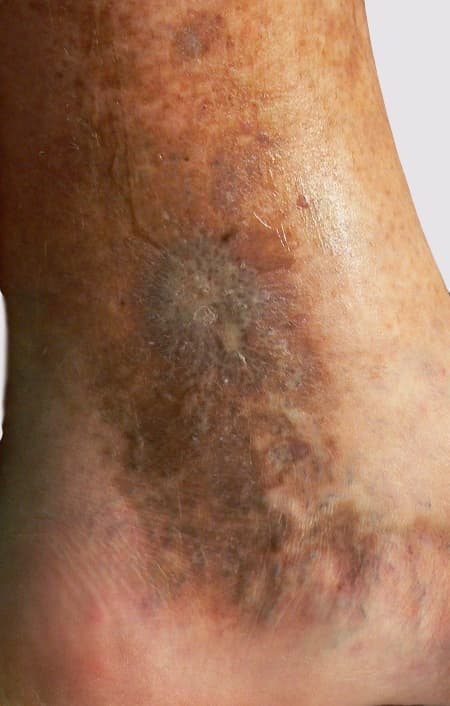

Scarring after healing of varicose vein ulcerScar left after healing

Taking so long to heal they will leave a scar once healed.

Most often the surrounding skin shows other changes of long-term varicose veins problems.

Pigmentation, skin and deeper tissue thickening are often present.